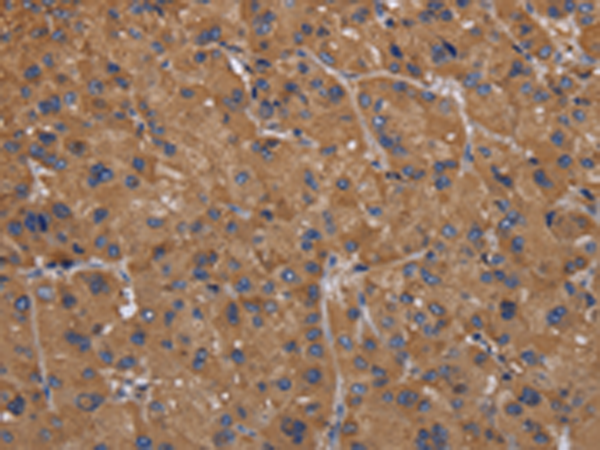

分类: 科研抗体货号: P08301别名: AMDD应用: IHC反应种属: Human